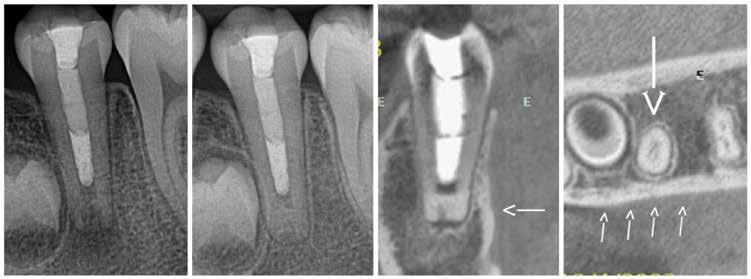

Proton density (left) and CBCT (right) images of apical lesion and furcation involvement at tooth #2. This tooth was clinically diagnosed with pulpal necrosis and a crack involving the furcation.

Proton density image showing improved image detail provided by dental dedicated MRI coil.

which perform notably better at imaging hard tissues such as bone and teeth, compared to more traditional MRI sequences.

While most dentists are likely familiar with the basics of how information is displayed on an MRI image, the adoption of ddMRI will require a mindset shift for virtually all dental team members who may utilize this new technology in their respective clinics. First, the grayscale is fundamentally different from that used for all X-raybased imaging. In MRI, soft tissues are commonly displayed as gray or bright white signals, while hard tissues, such as teeth and bone, are shown as very dark gray or black signals; air remains black. Furthermore, MRI offers the option to select from a variety of different sequences, each of which can produce a slightly different tissue grayscale and corresponding image. Some sequences, such as T1 or PD, do an excellent job of demonstrating detailed anatomical relationships. Other sequences, such as T2, do an excellent job of demonstrating the presence of fluid accumulation within tissues. Many available “Fat sat” or “STIR” sequences may selectively “zero out”, “suppress”, or “saturate” the signal of fat, which is traditionally very bright white on MRI images, to reveal the otherwise hidden signal from subtle fluid accumulation or inflammatory changes. Some of these specialized sequences may not accurately depict anatomic relationships, but are designed to be exceptionally sensitive to detecting inflammatory changes with a bright signal. The short T2 sequences mentioned above are beginning to depict the hard tissue differences between cortical bone and medullary bone, as well as the differences between tooth dentin and enamel. Developing, learning and using all these different sequence choices in concert is where the real research and diagnostic potential of ddMRI lies. t